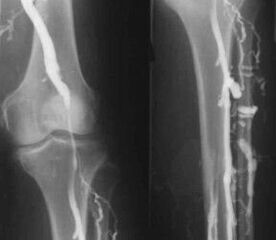

Най-често срещаният инструментален диагностичен метод е използването на ултразвуково изследване на венозните съдове на краката. Тази техника ви позволява да визуализирате съдовата система и да идентифицирате степента на прогресия на патологичния процес.

- Флебография.

- Фотоплетизмография.

Използването на венозна оклузионна плетизмография дава възможност да се определи обемът на кръвта във вените на долните крайници.